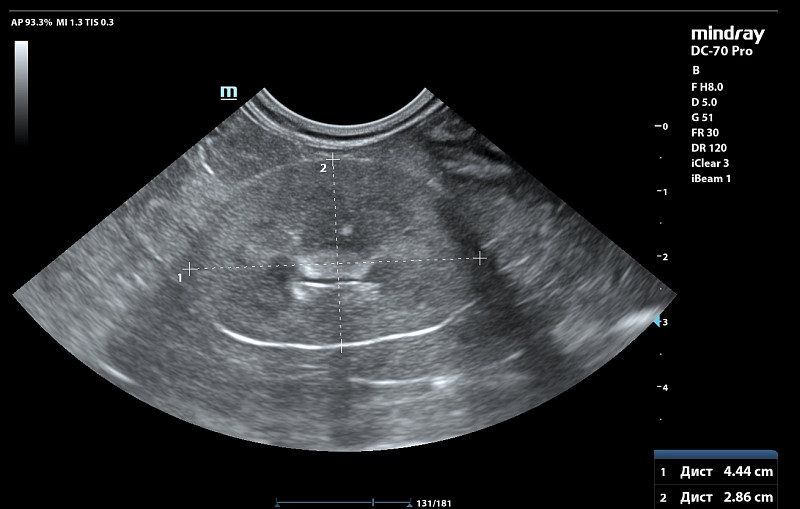

Здравствуйте! У абиссинской кошки, она астматик почти всю жизнь с дества на ингаляциях.Ей около 12 лет. На натуральном питании (бедро индейки, куринная шейка, сердечки индейки и свиной язык (только он в вареном виде, 2 года назад на таком питании все было в норме в анализах биохимияя и анализ мочи, но последние 4 мес я увеличила процент мяса в отношении, давая его 3 раза в неделю вместо языка в котором меньше фосфора)). 1.5 мес назад заметила запах у мочи и я решила подавтаь кантарен и в конце курса 8 кап на 8 кг она нагадила на пол и заметили что и запах пошел у мочи и мутная уже. Писала она 2 раза в день по многу. Крови не было. Резко стала пить больше воды по чашке дней 10 до амоксиклав. Вес не теряла ни 100 гр. Решили раз ничего серьезного подавать фураданин 1/2 таб 2 раза в день. Сильный запах почти сразу ушел. но мутность еще была, на 6 день лечения она покакала частично с поносом и тужилась и хотела остатки стула выдавить каках, стали вытирать ее и тогда словно спазм и она сделала 3 коротких метки и потом легла и пошла кровь. Крови было много, шла из мочевого канала часа три пока кошку не заперли в переноскеи в покое отсановилась уже после вет клиники. Врач хирург сказал что кажется много, а для ее веса немного крови. Ночью в ветклинике сделали узи почек и мочевого, сказали есть возврастные изменения ( они были и 5 лет назад и почки работали ок при этом), но ничего прям критичного по почкам по узи, смотреть анализы, мочевой стенка 0.3 мм вместо 0.1мм в прошлом когда кошка была 5 кг еще худее и здорова.

Сдали анализы после 8 ч голода ( не давали фурадонин 13 ч до аналиаза) Все анализы сдано 8 ч голода и 13 ч после отмены фурадонина (давали до 6 дней с пропуском 1 дозы тк 1 раз дала целую таблетку и ее вырвало. Прилагаю анализы и узи со снимками. Температуры у кошки не было, в р-не 38.1.